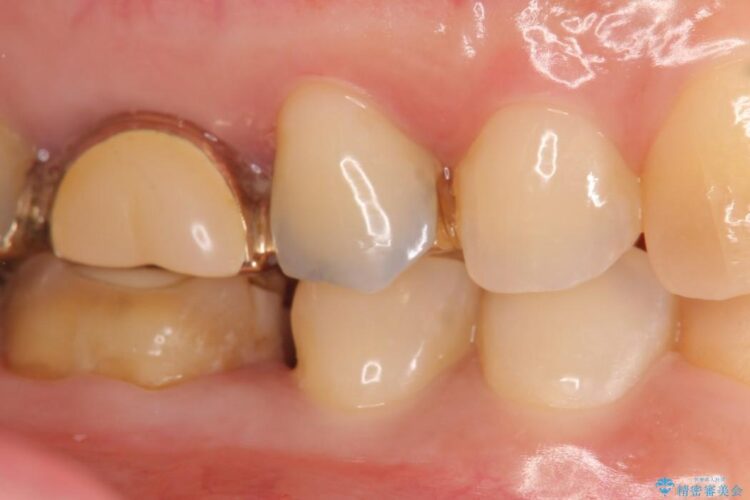

適合不良であるインレーを放置するリスクを患者様へ説明してご納得いただいた上で、オールセラミックインレーで治療を行うこととしました。

治療完了した歯でも、時間の経過や力的作用によってセメントが変性したり、隙間が空くことによって詰め物の下に虫歯が発生したりすることがあります。

そうならないためにも適合の良い剛性にも優れた素材を用いた治療を求められます。特にセラミックが使用されたインレーは見た目が自然なだけでなく適合性、剛性共に高い水準を持つためリスクを減らすことができます。

しかしセラミックは金属に比べて強い衝撃には弱く欠けたり割れてしまう可能性があるため注意が必要です。